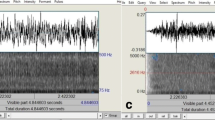

All four Sonomat sensors record the same signals, and this, in conjunction with their physical placement within the Sonomat (Fig. 1), creates a redundancy that permits the child to move around the bed in all directions while minimizing the amount of time off all sensors. Analysis requires signals from only one sensor. Figure 1 shows breathing movements (inspiration up) on the movement channel with breath sounds (first sound = inspiration) and heart sounds (vertical spikes) shown on the breath sounds channel. The breath sounds channel signal can be replayed through audio speakers/headphones and analyzed using spectrographic methods that allow visual display and measurement of the frequency components of the breath sounds.